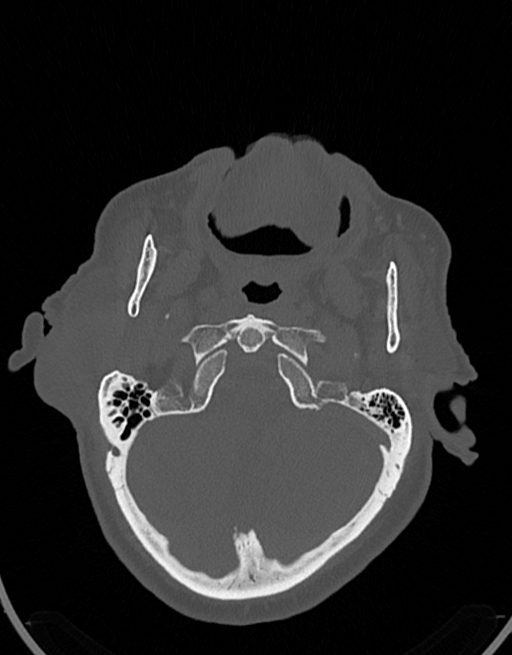

در سي تي اسکن اسپيرال نازو فارنکس با و بدون کنتراست (مولتي ديدکتور 16 با مقاطع ظريف و بازسازي هاي ساژيتال و کرونال):

– توده نسج نرمي به ابعاد mm 40 x 45 x 60 در ناحيه پاروتيد راست، با enhancement هتروژن پس از تزريق کنتراست مشهود است که مطرح کننده آدنوم پاروتيد مي باشد.

– شواهدي از تهاجم توده به استخوان و عروق اطراف مشهود نيست .

– کلسيفيکاسيون در ديواره شريان هاي کاروتيد دو طرف مشهود است .